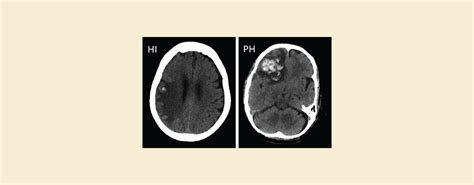

Infarct vs Hemorrhage: CT Scan Reveals the Difference – Knya

Intracerebral and Subarachnoid Hemorrhage

Intracerebral versus Subarachnoid Hemorrhage

Intracerebral Hemorrhage versus Subarachnoid Hemmorhage

Subarachnoid Hemorrhage vs Intracerebral Hemorrhae

Difference Between Intracerebral Hemorrhage and Subarachanoid Hemorrhage